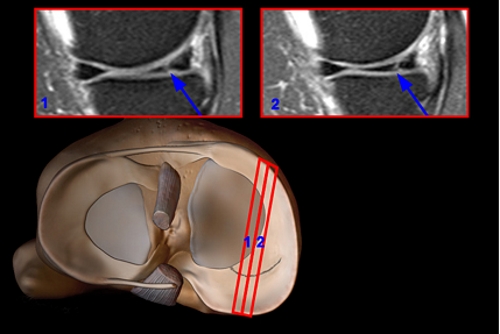

- компьютерная томография (КТ) или магнитно-резонансная томография (МРТ);

Если поврежден задний рог мениска, лечение начинается после тщательной оценки состояния суставных тканей. Магнитно-резонансная томография является информативным методом, так как не создает лучевой нагрузки. При необходимости выполняется артроскопия — эндоскопический метод, позволяющий осмотреть колено как с диагностической, так и с лечебной целью. Артроскопия позволяет визуально оценить состояние коленного сустава. Перед процедурой необходимо сдать ряд анализов. Исследование может проводиться в амбулаторных условиях.